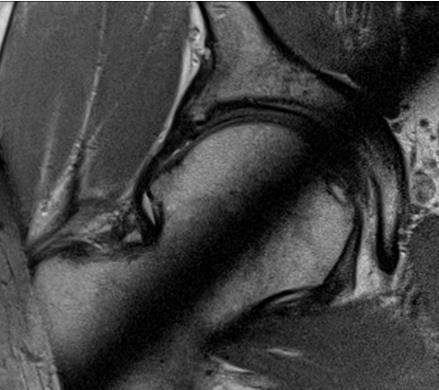

Do charakterystycznych objawów patologii widocznej na poniższych obrazach tomografii rezonansu magnetycznego należą: 1) ból okolicy lędźwiowej; 2) ból promieniujący do kończyny dolnej wzdłuż bocznej powierzchni uda, tylnej powierzchni podudzia i pięty; 3) osłabienie czucia powierzchniowego dotyku w okolicy spoidła I i II palca stopy; 4) osłabienie siły zgięcia grzbietowego stopy; 5) osłabienie siły zgięcia podeszwowego stopy. Prawidłowa odpowiedź to:

Pytanie 69